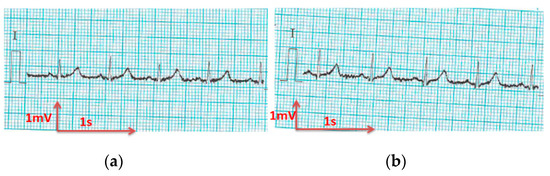

3.3.1. ECG Recorded by Portable Medical Device

- For all textile electrodes, ECG signals were recorded by a portable medical device as well as with a low-cost, Arduino-based open source device. Using portable medical devices, all electrocardiographic P, T waves, and QRS complexes were identifiable, despite higher contact impedance of PEDOT:PSS textile electrodes. Signal quality analysis by cardiologist showed that these textile electrodes, used in ambulatory conditions for heart monitoring, allow the detection of rhythmic disorders (Atrial Fibrillation, ventricular tachycardia, etc.) and conduction troubles (sinus dysfunction, atrioventricular block etc.), and can detect myocardial ischemia (ST segment underlining) in some cases. Such a system, integrated into garments, can be used in real-time and in continuous mode to monitor the user’s heart in a comfortable way, and to detect possible issues that, with additional analysis if needed, could be avoided, such as strokes. Regarding low-cost devices, assuming that high contact impedance between the skin and textile electrodes is the cause of no detectability or noise and severe distortion of cardiac waveforms, it was concluded that the amplifiers of the low-cost device are not appropriate to record ECG of our developed PEDOT:PSS textile electrodes, and also, that of commercial silver-plated electrodes. Textile electrodes inherently provide high contact skin-electrode impedance because the ECG recording is based only on natural skin moisture and perspiration and without any added gel. Therefore, compatible recording amplifiers with high input impedance are required to compensate for the high contact impedance skin-electrode, which is related to the low mobility of ions across the highly-resistant stratum corneum layer of the skin that causes weak conductivity between the electrodes and the skin.